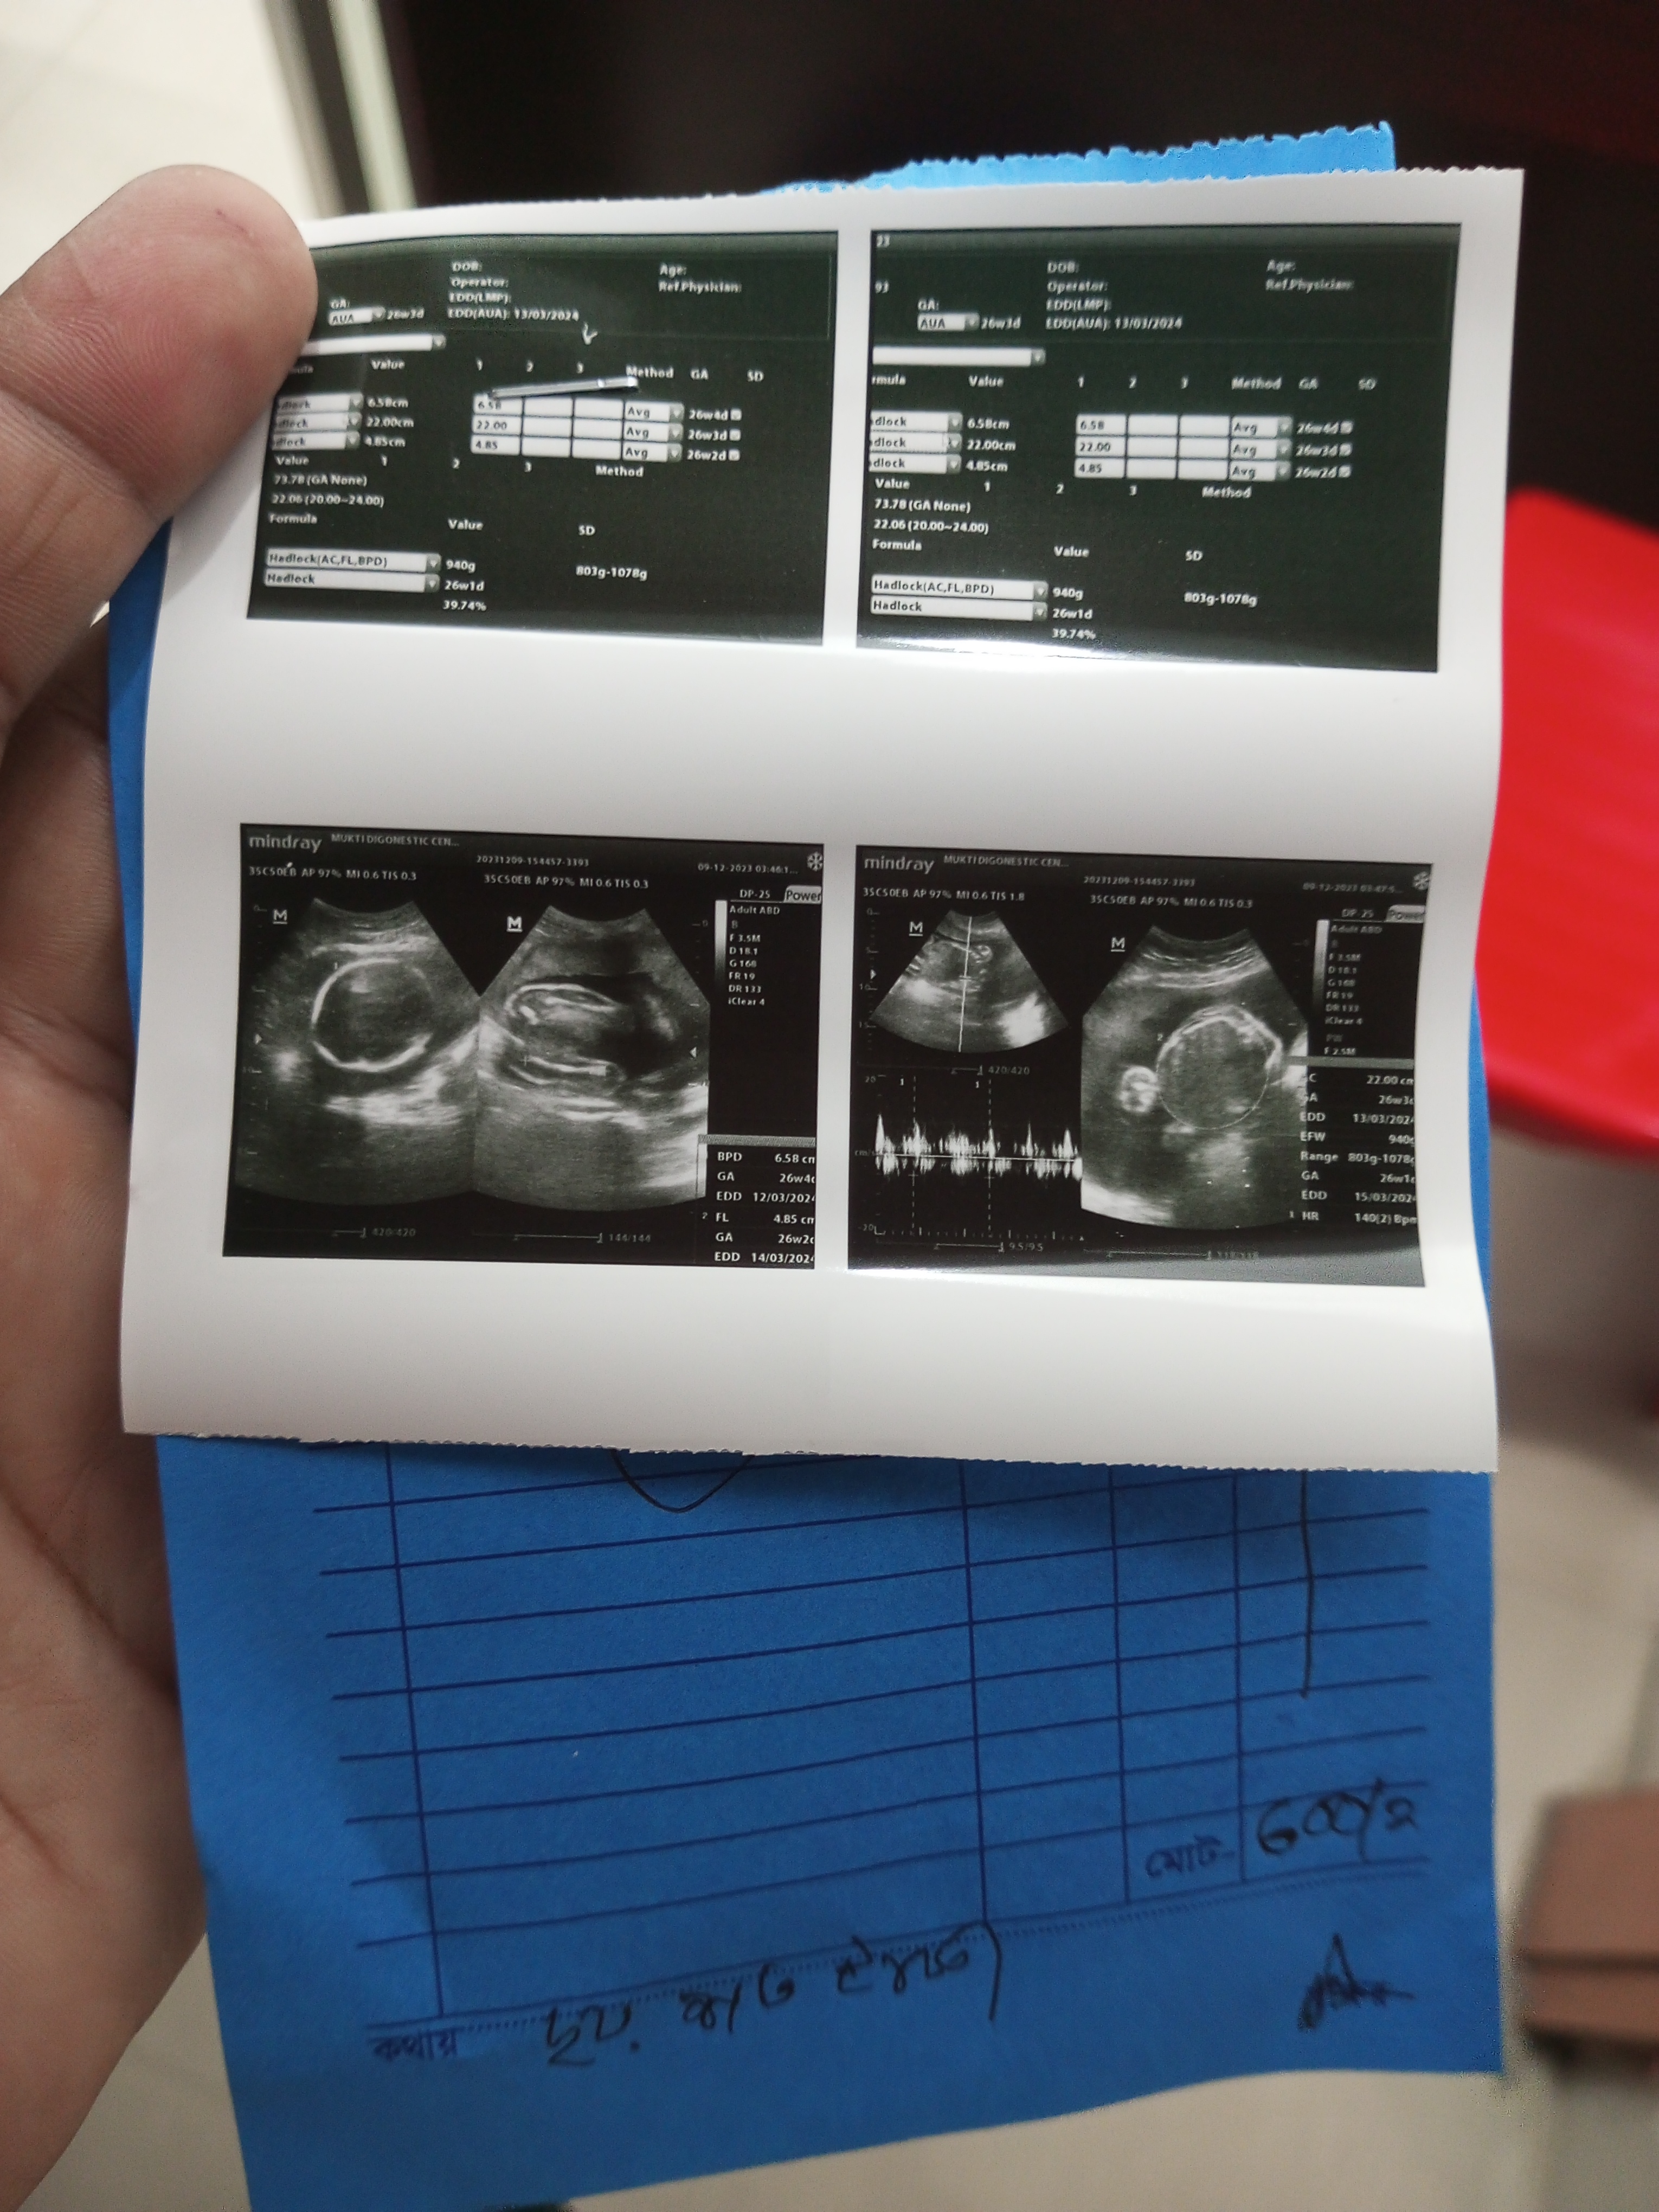

যেহেতু পাঁচ মাস পার হয়ে গেছে, প্রায় ছয় মাসের পাশাপাশি অবস্থান। এজন্য উনার কাছে এসেছি বাবুর অবস্থান জানার জন্য। তাই উনে তিনটা টেস্ট দিলেন। আল্টাসনো করতে হবে রক্ত পরীক্ষা আর ইউরিন পরীক্ষা। রক্ত পরীক্ষা করার বিষয়টা আমার কাছে বেশ ভয় লাগে কারণ ইঞ্জেকশনের মাধ্যমে রক্ত বের করাটা আমার কাছে বেশ কঠিন। তবুও টেস্ট বিষয় ভয় পেতে গেলে চলবে না,এদিকে আমার হাজবেন্ড আমার পাশে থাকলে মনে বেশ সাহস থাকে।

কিছুটা সময়ের মধ্যে পর্যায়ক্রমে টেস্ট গুলো করা হয়ে গেল। আল্টাসোনো তে ম্যাডাম জানিয়ে দিল আমার গর্ভে মেয়ে সন্তান রয়েছে। কথাটা শোনার পর কিছুটা ভয় কিছুটা আনন্দ মনের মধ্যে কাজ করল। এরপর আমরা সমস্ত রিপোর্ট পাওয়ার আশায় বসে থাকলাম।

এরপর ম্যাডাম আমার রিপোর্ট দেখলো। বাচ্চার ওজন সাড়ে পাঁচ মাস বয়সের ৯০০ গ্রাম পার হয়েছে বলে বললেন ঠিক আছে। এতে চিন্তার কিছু নেই। এখন থেকে ঠিকঠাক ভাবে খাওয়া দাওয়া করবেন, হাটাহাটি করতে বললেন। হওয়ার আগ পর্যন্ত ভালো পর্যায়ে এসে যাবে। আর বেশ কিছু ওষুধ লিখে দিলেন পাশাপাশি দুধ ডিমসহ বিভিন্ন প্রজেক্ট খাবারের কথা বলে দিলেন। আর যাবতীয় নিয়ম বলে দিলেন। এরপর আমরা সেখান থেকে বিদায় নিয়ে চলে এলাম। আশা করি আপনারা সকলে আমার এবং আমার বাচ্চার জন্য দোয়া করবেন। যেন সুস্থ অবস্থায় সুস্থ সবল নেক হায়াত সম্পন্ন একটি বাচ্চা আল্লাহ আমাকে দান করেন।